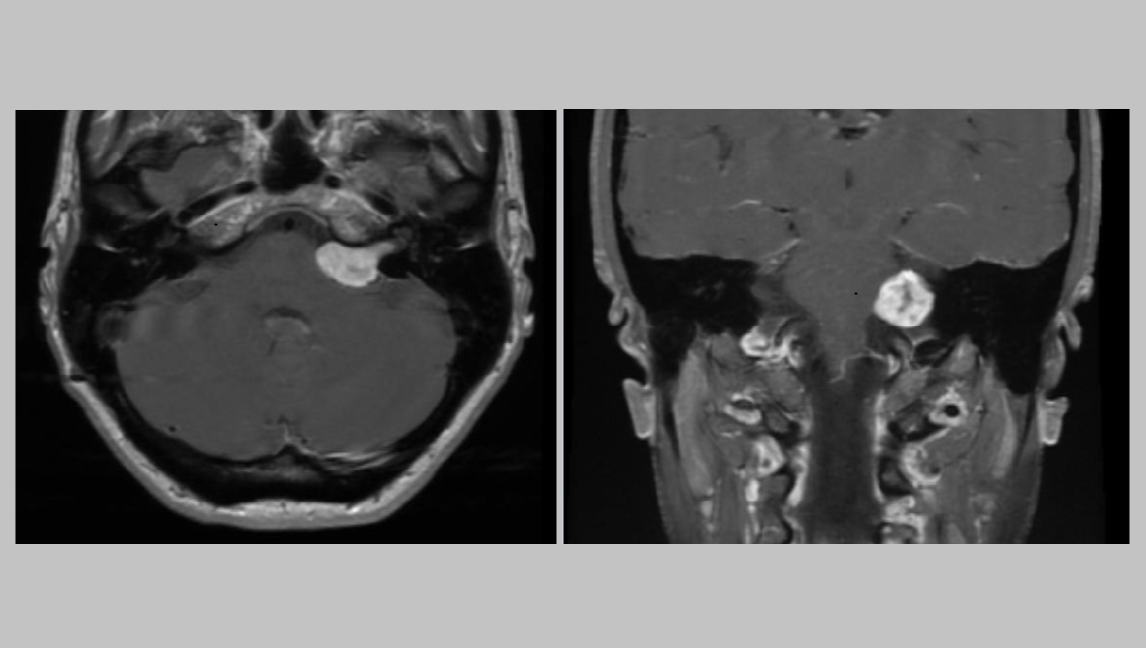

Prior to the pandemic, I was diagnosed with a treatable skull-based tumor that's compressing blood vessels, nerves, the brain stem, and other critical structures. At the time, I was already struggling physically, emotionally and financially because of several chronic conditions that include rare ones.

The tumor was originally misdiagnosed, which resulted in a delay in care for almost a year. During that time, I struggled with a lot of symptoms that adversely impacted my work and finances. Eventually, once I knew what I was dealing with, I found ways to work around the symptoms.

The more serious chronic conditions have gone untreated for far too long. The tumor symptoms are worsening and making it harder for me to work. I was last told that it's growing faster than normal. I have no idea today how much it has grown since the last scans, which were performed more than a year ago.